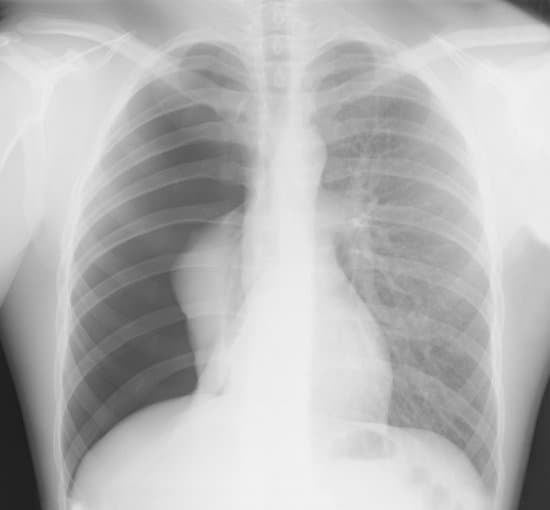

기흉의 진단은 주로 환자의 증상, 병력 청취, 신체 검사에 기반합니다. 가슴 X-레이, 컴퓨터 단층촬영(CT) 스캔 등의 영상 진단 방법이 사용될 수 있으며, 이를 통해 공기의 유입 및 폐의 쪼그라듬 정도를 확인할 수 있습니다.